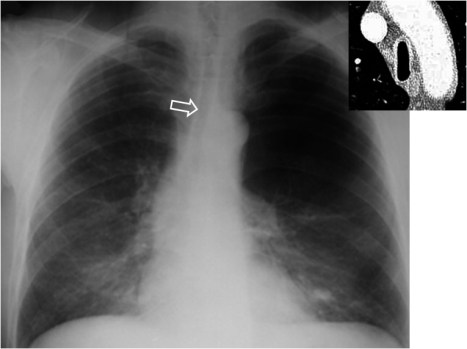

SIGNO DE LA TRÁQUEA EN SABLESABLESigno de enfermedad pulmonar obstructiva crónica en la radiografía posteroanterior del tórax. Hace referencia a la deformidad relativamente persistente que consiste en el adelgazamiento de la luz traqueal en el eje laterolateral, así como un cambio brusco de calibre en la porción cervical.

En este paciente vemos también otros hallazgos de esta enfermedad, hiperlucencia en el campo superior izquierdo por bullas y patrón intersticial (“patrón sucio”) en bases.